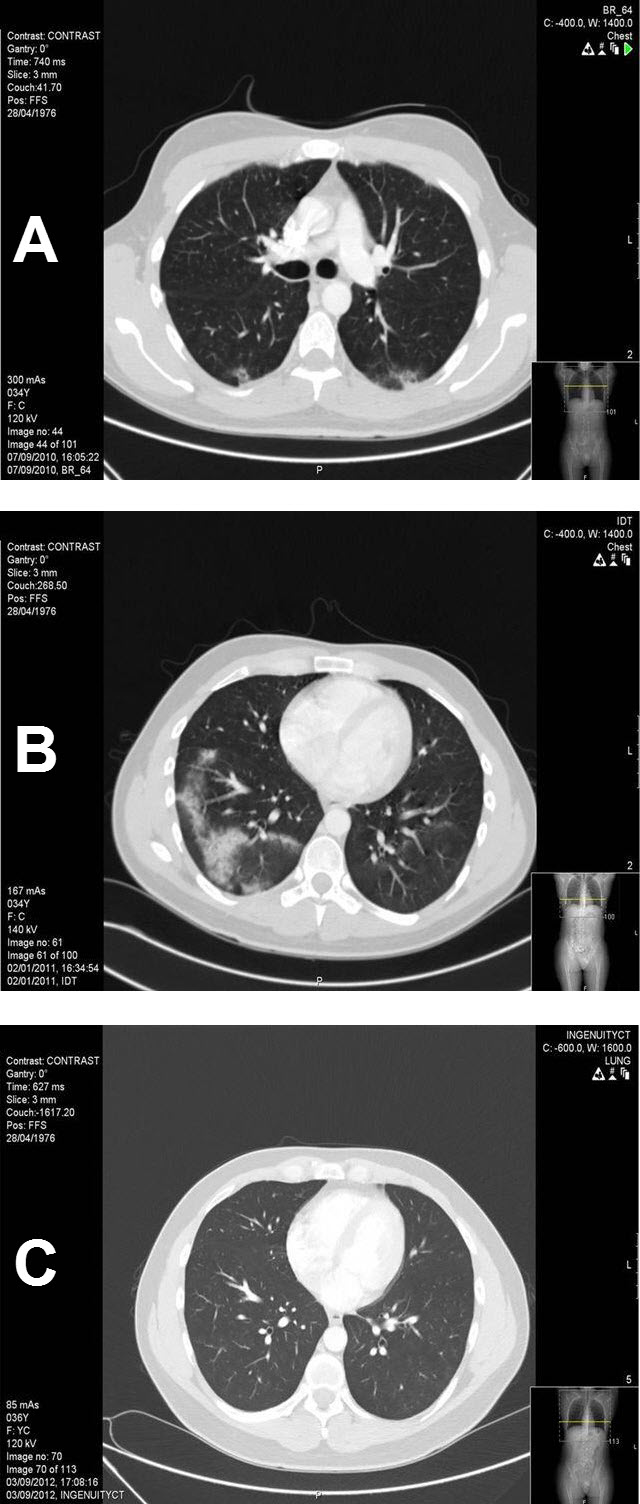

Figure 1.

A CT Scan Following Completion of BEP Regimen (cumulative bleomycin dose 240 units) at 2 Months (A), 5 Months (B), 10 Months (C).

A) 2 months: Interstitial alveolar infiltrates in the posterior, hanging parts of the right and left lower lobes; B) 5 months: Alveolar shadows in various sizes confined to both lung bases, more on the right side but also on the right middle and upper lobes—clear worsening compared to 1A; C) 10 months: Clear regression and improvement in the right lower and right middle lobes.